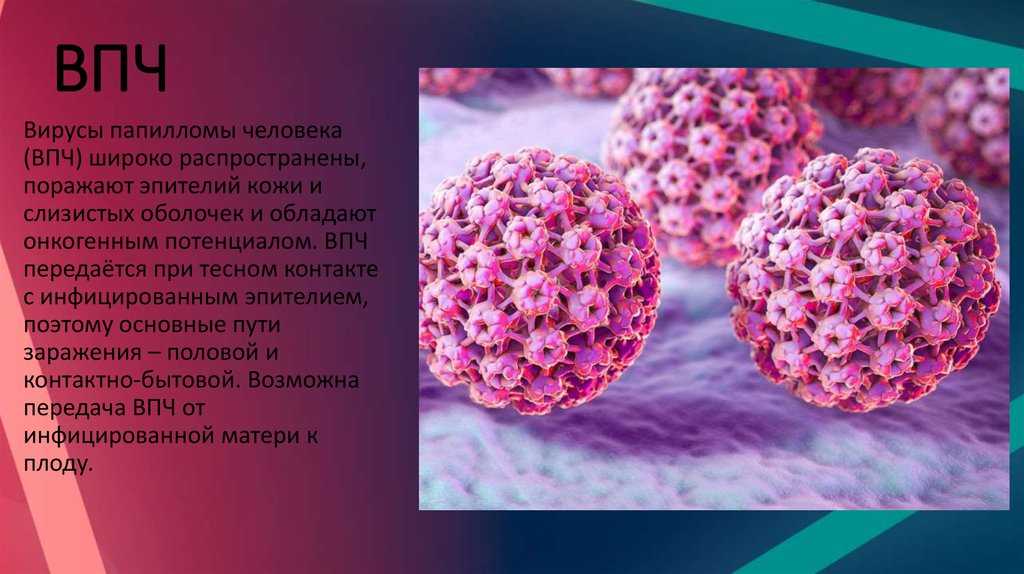

Факторы Риска ВПЧ: Визуальный Обзор и Информация

Раздел: Кладезь мудрости